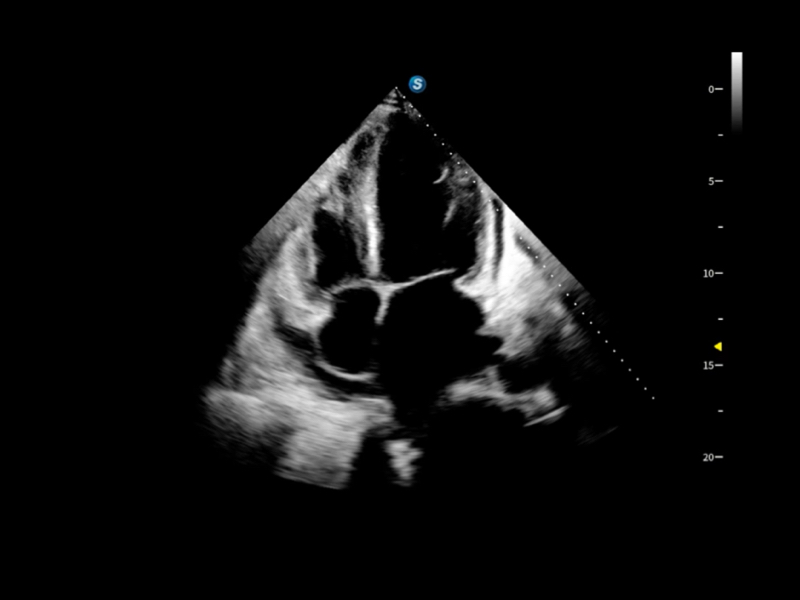

作为开立医疗全新打造的超高端旗舰超声产品,从探头抬起唤醒开启扫查到多维探头发射接收,通过先进的场成像发射、自适应聚合重建等技术,基于RF Data原始射频数据在图像生成、高端功能等方面实现突破,提供多科室综合临床解决方案。

独有场成像发射技术

自适应聚合重建技术

独家XPUs混合硬件架构